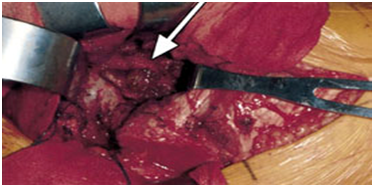

Grossly, pigmented villonodular synovitis appears as a proliferative synovial process with brownish villo-nodular fronds in the affected joints (Figure 3).2 Multiple yellow to brown nodules could be detected in localized types and in the pes anserine bursa (Figure 4). Histopathologically, the tumor is generally represented by many mononuclear histiocytic cells and irregularly interspersed multinucleated giant cells. Hemosiderin pigments could also be detected. Some foamy histiocytic cells may individually interspersed or form clusters (Figure 5).8 Osseous, cartilaginous, and soft tissue involvement was also seen .Fine needle aspiration cytology reveal a few clustered and scattered plump spindle cells containing hemosiderin-pigments and several scattered multinucleated giant cells (Figure 6).

Figure 3 Photograph showing characteristic hypertrophic synoviumv (arrow) and villo-nodular fronds in pigmented villonodular synovitis.